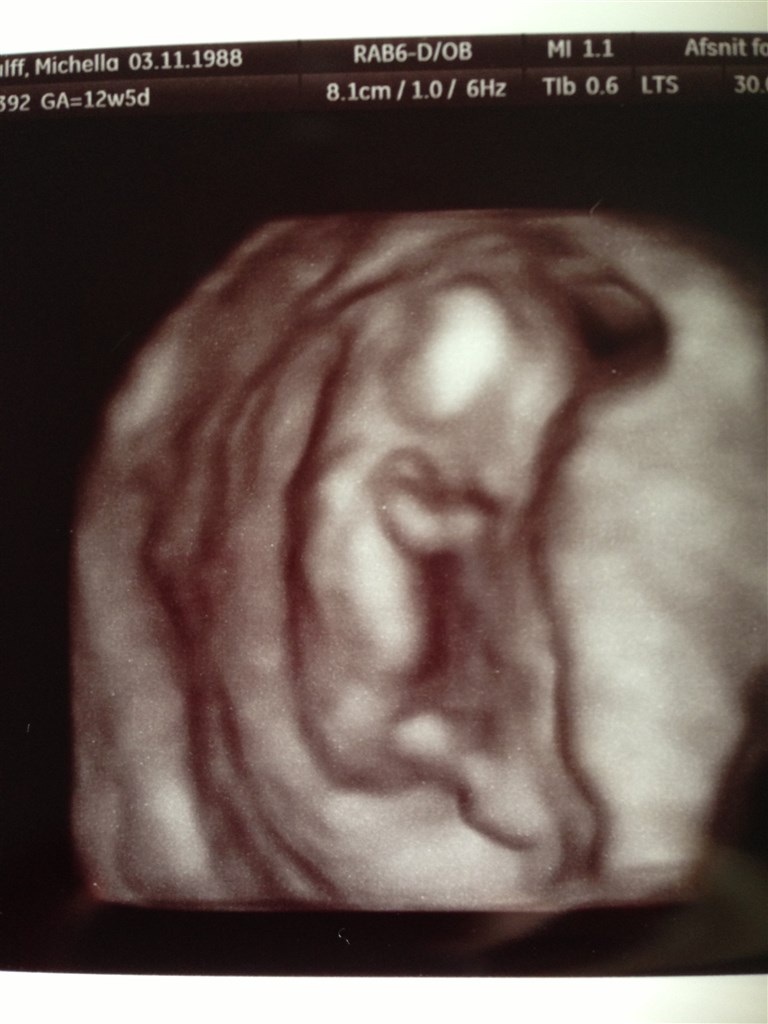

Efter ca. 30 min scanning fik vi afvide alt så rigtig fint ud og den lille stædige baby som ikk ville det samme som scanningsdamen havde fine tal på 1:18916 samt alt det andet den skal ha. Vi er så glade. Vi fik endda lige 2 3D billeder med samt 2 alm.

Vedhæftede fotos (klik for at se i fuld størrelse)